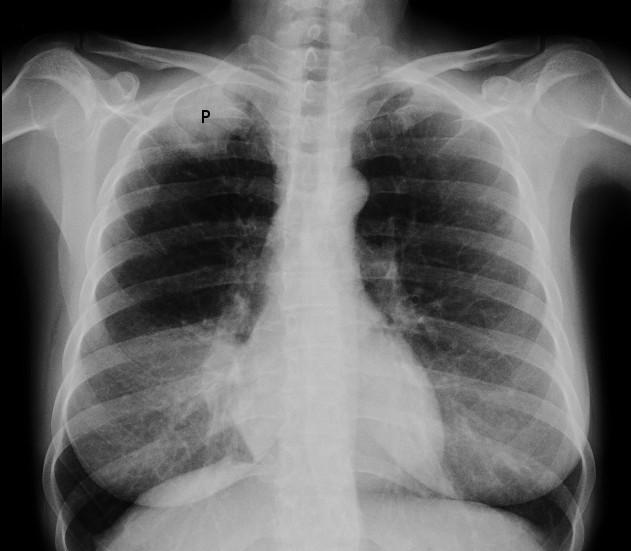

X-ray image of Pancoast tumour

© Jmarchn (Own work), CC BY-SA 3.0, via Wikimedia Commons

Pancoast's syndrome is usually caused by a malignant neoplasm of the superior sulcus of the lung which produces destructive lesions of thoracic inlet along with involvement of brachial plexus and stellate ganglion. These cancers are rare, accounting for fewer than 5% of all lung cancers. The neoplasm is usually bronchogenic in origin (about half are squamous cell carcinomas, half adenocarcinomas).2